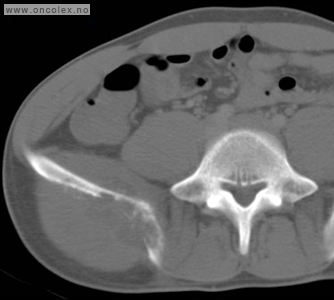

Vevsprøve fra svulsten tas for å stille diagnosen. Oftest trenger man å ta bilder underveis når man tar vevsprøver for å sikre at prøvene blir tatt fra riktig sted og på riktig måte. Ved mistanke om bensarkom er det mest vanlig å bruke CT som hjelpemiddel.

Ved bensarkomer med bløtdelskomponent utenfor knokkel, eller med nedbryting av knokkelens overflate med åpning inn til svulsten, kan det gjøres ultralydveiledet vevsprøve

Hvis knokkelens overflate er intakt er ikke svulsten synlig på ultralyd. CT-veiledet vevsprøve er da foretrukket metode.

Ved CT- og ultralydveiledet vevsprøve vil man som regel ta prøve med både grovnål til histologisk undersøkelse og finnål til cytologisk undersøkelse.